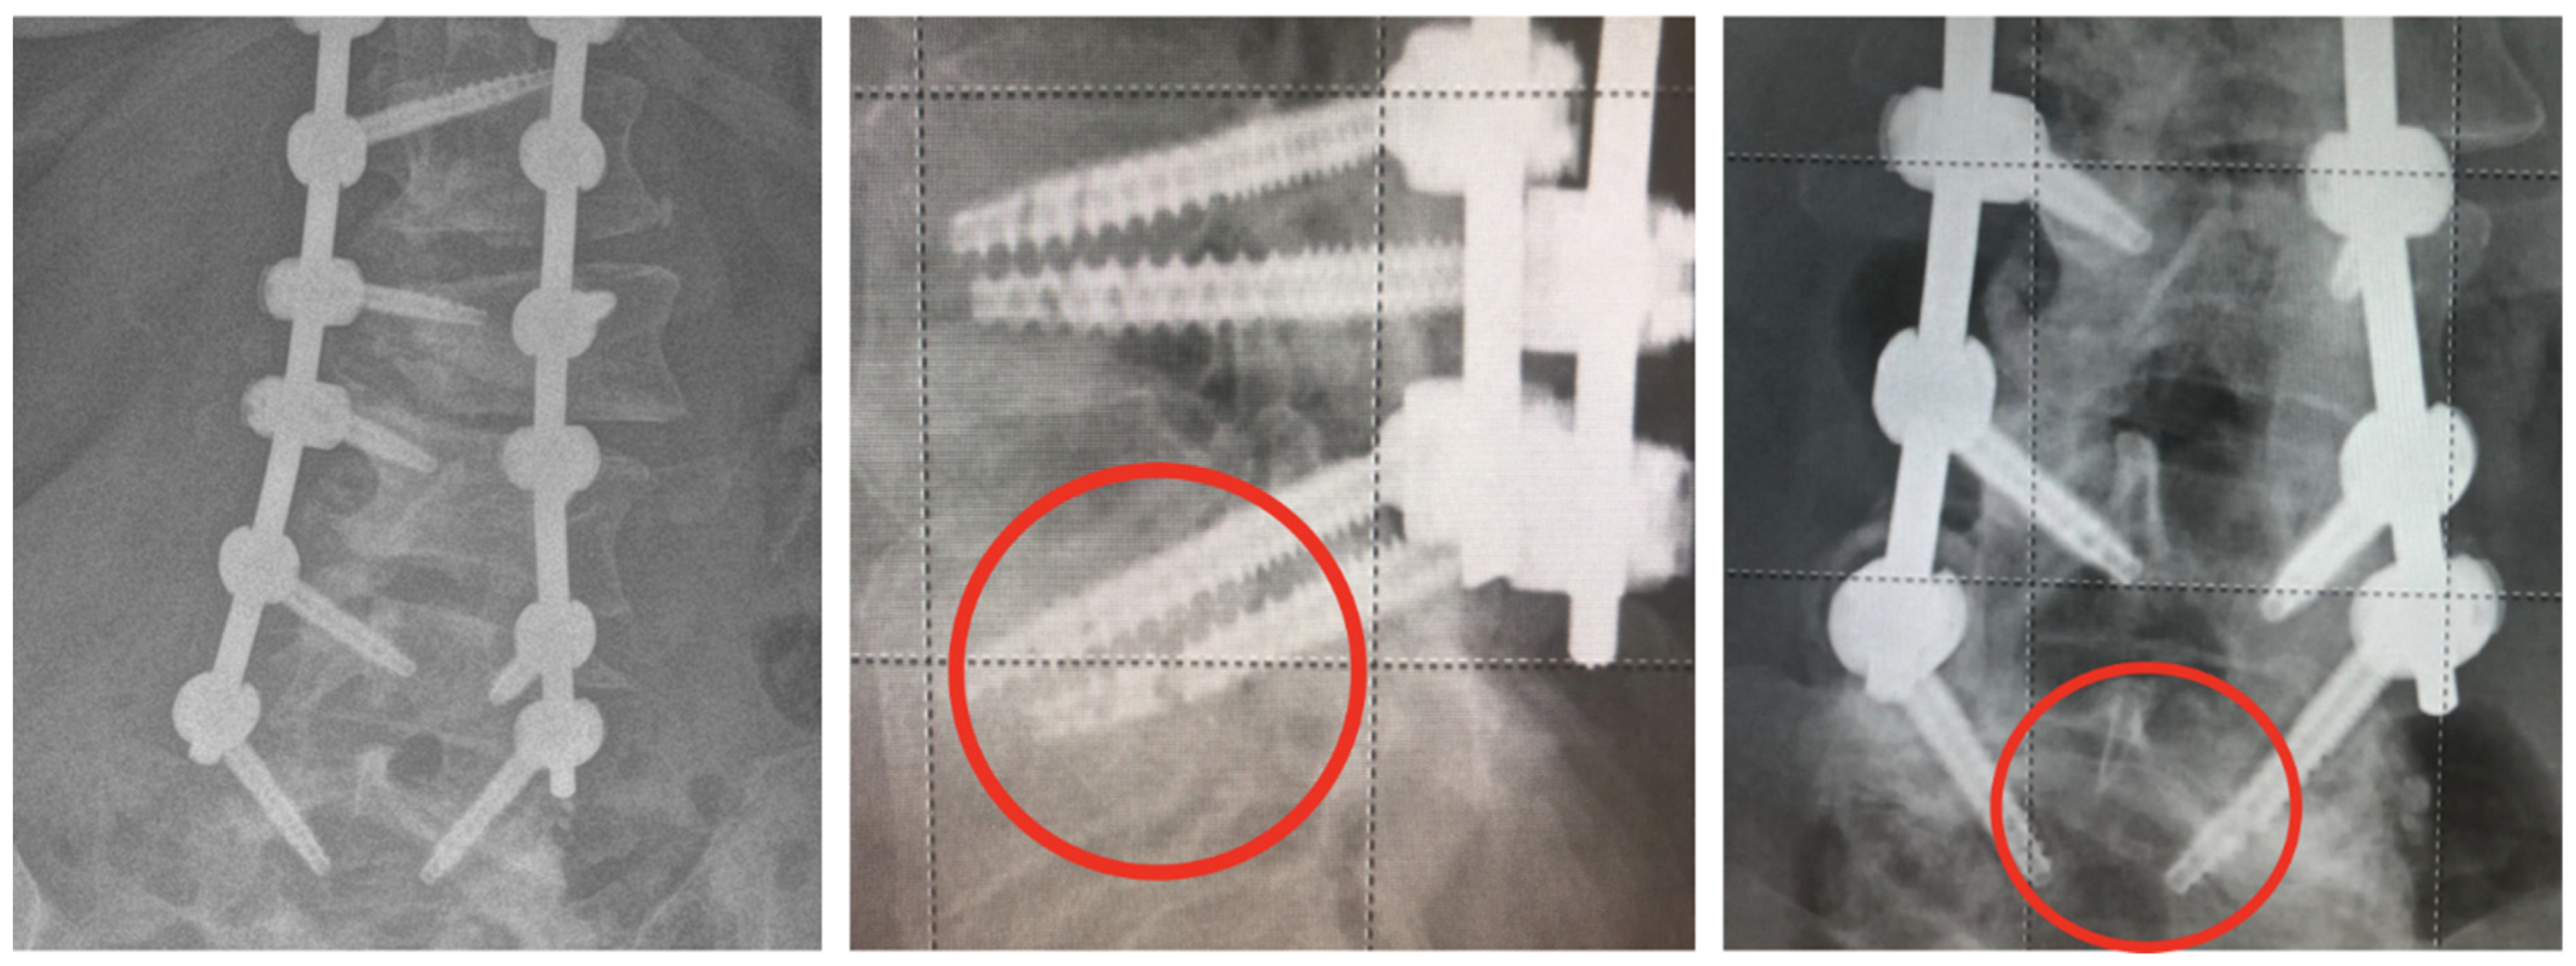

3.4. Complications